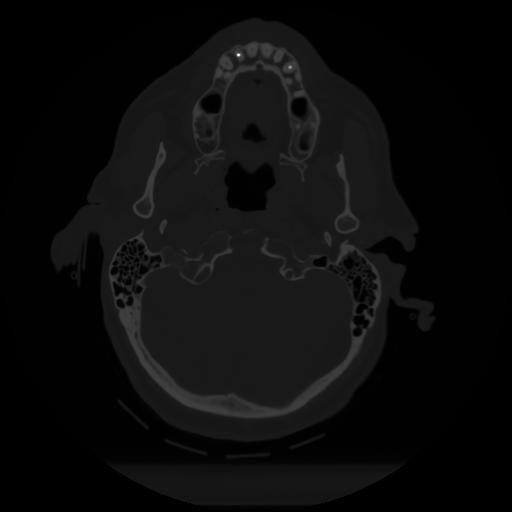

12 P.BLANDAS,,Vol,0.5,P.BLANDAS,,